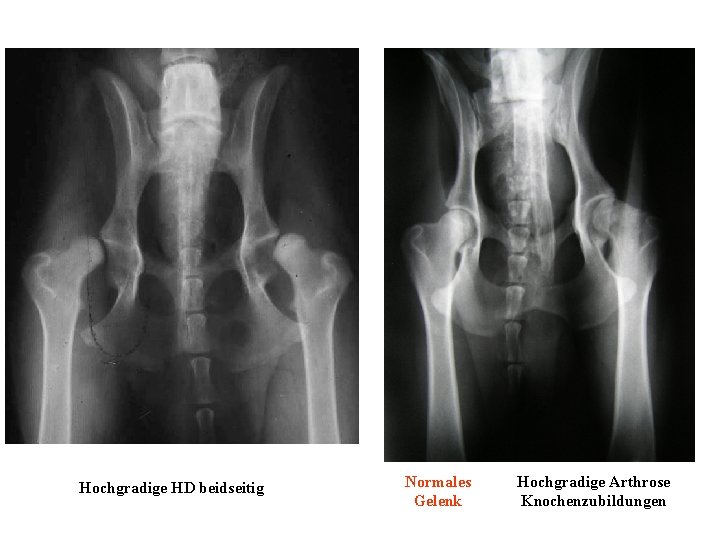

Hochgradige HD beidseitig Normales Gelenk Hochgradige Arthrose Knochenzubildungen

Normales Gelenk Hochgradige Arthrose